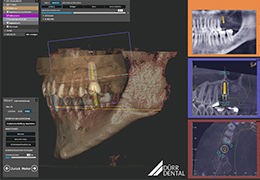

View X-Ray CT & MRI Scans Fast and Easily

Designed for surgeons, Pro Surgical 3D makes it easy to view patient scans quickly. Pro Surgical 3D facilitates the optimal 3D treatment and assessment workflows based on X-ray CT and MRI scans – and best of all, it’s FREE!

High-quality and fast 3D reconstruction and 3D rendering

Performs 3D reconstruction and volume rendering.

Instant and interactive surface extraction and export to STL and PLY formats.

Side-by-side comparative assessment for pre- and post-operative scans.